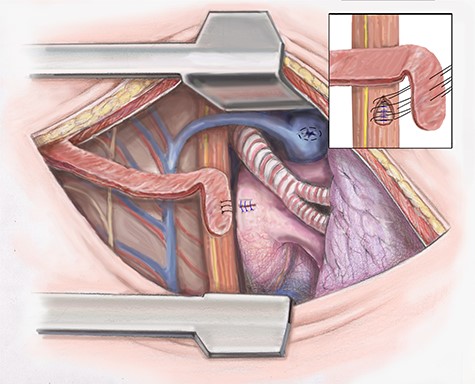

The descending aorta is exposed and 1 inch above the diaphragm a purse string suture is placed. The cannula is inserted and the suture secured. The pericardium is opened. If any purulent material is encountered, it is sent for culture. A 2–0 Ethibond purse string suture is placed on the lateral surface of the right atrium and cannulation is performed (Fig. 2).

Artist illustration shows closure of atrial portion of fistula.

Once dissection of the esophagus is complete the patient is placed on CPB and fully heparinized. The fistula tract of the left atrium is opened and necrotic tissue debrided. It is essential that during debridement the surgeon skives toward the esophagus. A primary repair of the left atrium is then completed in an interrupted fashion using 4–0 prolene (Fig. 2). The heart is filled slowly and weaned off CPB.